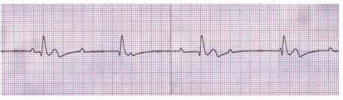

A referida paciente evolui com colapso circulatório, pulso ausente e demonstrado no eletrocardiograma apresentado. Conforme essa análise, conclui-se ser o ritmo da parada cardíaca é